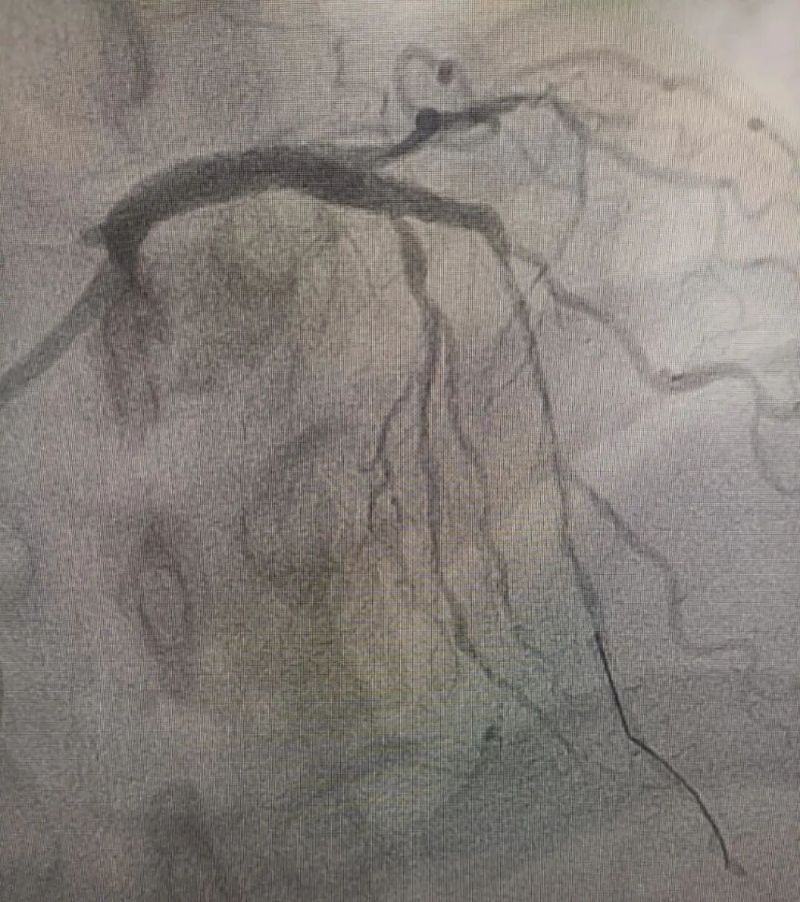

術(shù)中造影顯示,左主干至前降支近段重度狹窄——這正是導(dǎo)致心臟缺血、誘發(fā)室顫的“罪魁禍?zhǔn)住?。主動脈球囊反搏植入、球囊擴張、支架植入......介入團(tuán)隊精準(zhǔn)操作,一氣呵成。堵塞的血管順利開通,血流重新涌動,這顆一度瀕臨停跳的心臟終于重獲生機。

冠狀動脈造影圖

術(shù)后(左主干至前降支近段原狹窄消失)